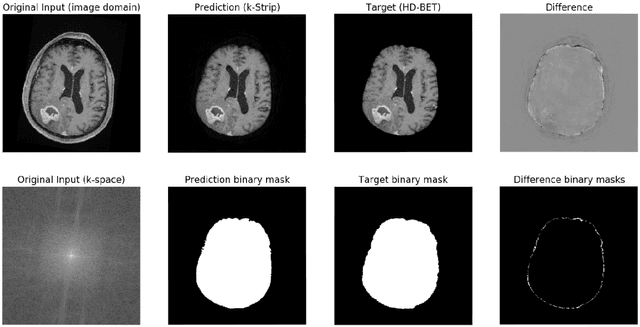

Abstract:Objectives: Present a novel deep learning-based skull stripping algorithm for magnetic resonance imaging (MRI) that works directly in the information rich k-space. Materials and Methods: Using two datasets from different institutions with a total of 36,900 MRI slices, we trained a deep learning-based model to work directly with the complex raw k-space data. Skull stripping performed by HD-BET (Brain Extraction Tool) in the image domain were used as the ground truth. Results: Both datasets were very similar to the ground truth (DICE scores of 92\%-98\% and Hausdorff distances of under 5.5 mm). Results on slices above the eye-region reach DICE scores of up to 99\%, while the accuracy drops in regions around the eyes and below, with partially blurred output. The output of k-strip often smoothed edges at the demarcation to the skull. Binary masks are created with an appropriate threshold. Conclusion: With this proof-of-concept study, we were able to show the feasibility of working in the k-space frequency domain, preserving phase information, with consistent results. Future research should be dedicated to discovering additional ways the k-space can be used for innovative image analysis and further workflows.